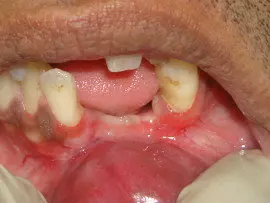

Frenectomy a minor procedure done to remove high frenum, which causes pulling of gum tissue [gingival recession]. High frenum also causes  spacing in between teeth creating cosmetic & functional problems.

Vestibuloplasty is also a similar procedure but intended to remove high attached tissue  to get a good depth.

Recently with use of soft & hard tissue lasers both these procedure have become very easy, bloodless & comfortable to the patient,